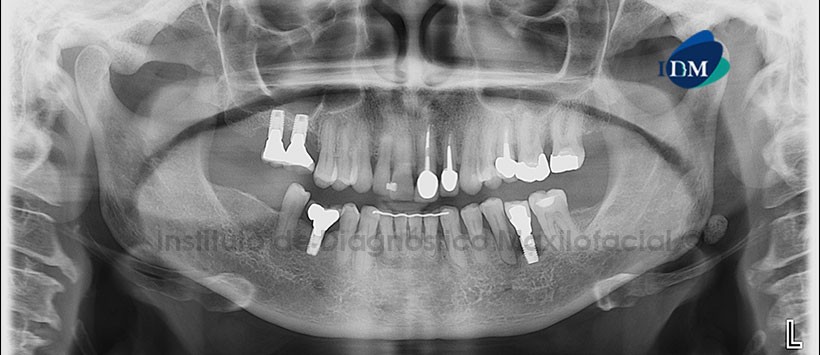

A la evaluación de la radiografía Panorámica (Figura 1) se observa presencia de implantes y prótesis sobre implantes con presencia de defectos óseos severos de tipo angular en zonas correspondientes a piezas 17, 16, 36, 45. Se aprecia además piezas con tratamiento de conductos radiculares y restauraciones protésicas.